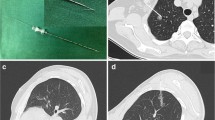

A 16–20 G coaxial double-cavity puncture needle (Fig. 1, Hefei Sipin Technology Co., Ltd., Hefei, China) was used to inject 0.1 mL magnetic fluid of different concentrations and 0.1 mL curing agent simultaneously. After the gel was formed, the gel properties were measured again using an MCR302 rheometer to compare the mechanical properties of the gel before and after the addition of magnetic powder, and the attraction between the pursuit magnet and the magnetic gel was measured using a UTM6202 electronic universal testing machine (Shenzhen Sansi Zongheng Technology Co., Ltd., Shenzhen, China).

(a) Coaxial double-cavity puncture needle (inner cavity: 20 G; outer cavity: 16 G). (b) Operation method: The needle is divided into two parts, an inner and an outer cavity. The horizontal syringe contains the magnetic fluid, connected with the inner cavity; the longitudinal syringe contains the calcium gluconate solution, connected with the outer cavity. The two syringes are injected at the same time, and the magnetic fluid in the inner cavity enters the lung tissue under the calcium gluconate solution to form gel.

Results of short-term localization

X-ray observation of magnetic gel

All three rabbits in the group assigned to the short-term localization were successfully injected with magnetic gel to locate the imaginary lung nodules. No diffusion of magnetic fluid or displacement of the magnetic gel was observed under X-ray (Fig. 5).

Observation of gross specimens

When observing lung tissue visually, the injection site was seen to contain black magnetic fluid without diffusion after injection. A small amount of bleeding with no hematoma was observed. The magnetic fluid solidified in the lung to form a mass of gel. Its shape and position did not change with external force when the injection site was touched with the tip of the forefinger (Fig. 6).

A pursuit magnet was used to provide an applied magnetic field that could attract the magnetic gel, and this drew the lung tissue together to protrude from the lung surface (Fig. 7). No tearing or wound was observed in the lung tissue and no magnetic gel escaped after removal of the pursuit magnet.

Results of long-term localization

X-ray observation of the magnetic gel

All 12 rabbits were successfully injected with magnetic gel to locate imaginary lung nodules. No complications such as bleeding or pneumothorax occurred during the operation. The condition of the rabbits was good after the operation, with no coughing or dyspnea observed. No diffusion of magnetic fluid or displacement of the magnetic gel was observed under X-ray within 7 days (Fig. 9).

Observation of gross specimens

On days 1, 3, 5, and 7 after the operation, the rabbits were euthanized and the chest was opened. A pursuit magnet was used to provide an applied magnetic field to the lung surface to observe the localization effect. We observed that the magnetic gel was attracted by the applied magnetic field, and that the local area was involved. The lung tissue where the hypothetical SPN located was protruded from the surface of the lung (Fig. 10).